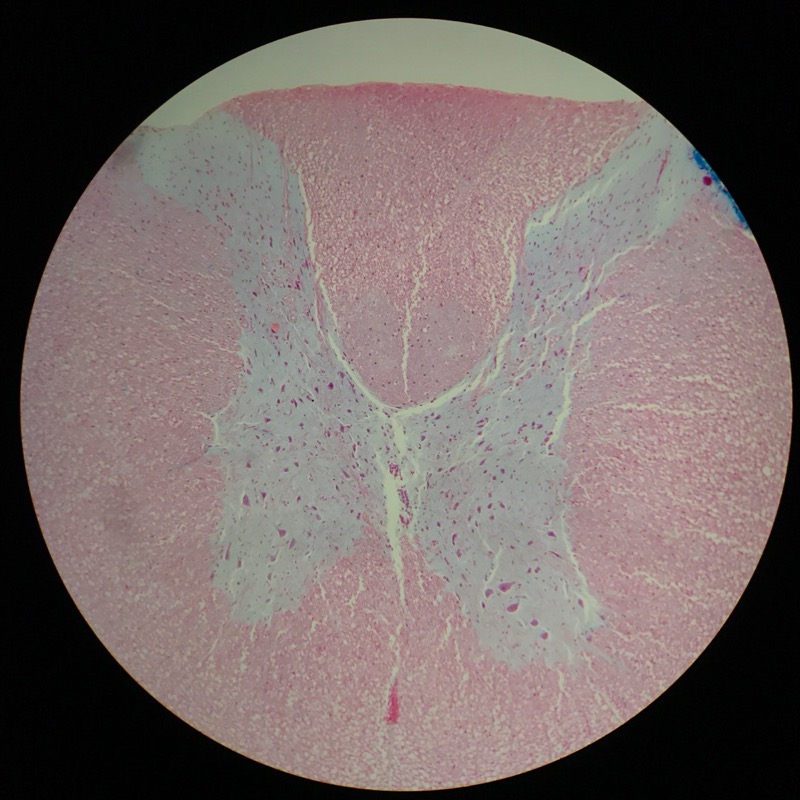

| 1:8:5 | Medulla Spinalis Galiomycin/Azan | ![]() ![]() ![]() ![]() |

| 1:8:6 | Medulla spinalis, silverfärning | ![]() ![]() ![]() ![]() ![]() ![]() |